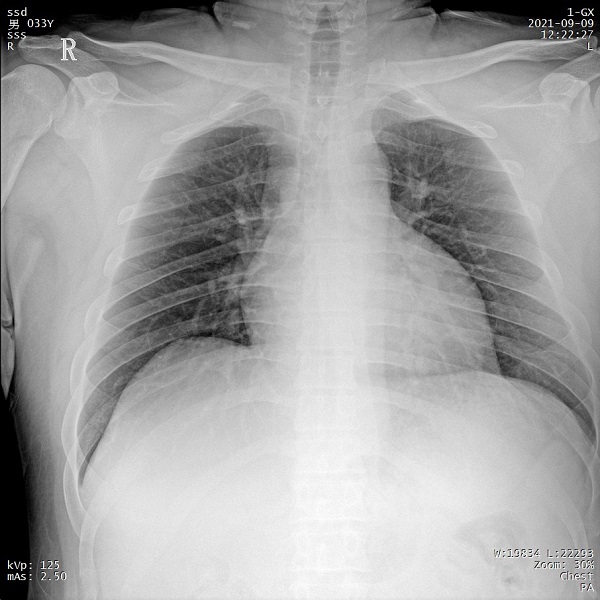

一、肥胖患者、組織較厚部位清晰成像

管電流大小與設(shè)備輸出X射線的能力相關(guān),管電流越大,設(shè)備輸出的射線量越充沛。PLX5500的管電流達(dá)到了710mA,輸出的射線能夠滿(mǎn)足各體型患者的拍攝需求,即便是體重達(dá)上百公斤的患者,也能夠獲得清晰的圖像。

三、支持高千伏攝影 肺部紋理更有層次

PLX5500系列移動(dòng)DR的可調(diào)千伏達(dá)到150kV,在達(dá)到一定高電壓后,與骨骼相重疊的軟組織或骨骼本身的細(xì)小結(jié)構(gòu)及含氣的管腔等,均可清晰顯示。